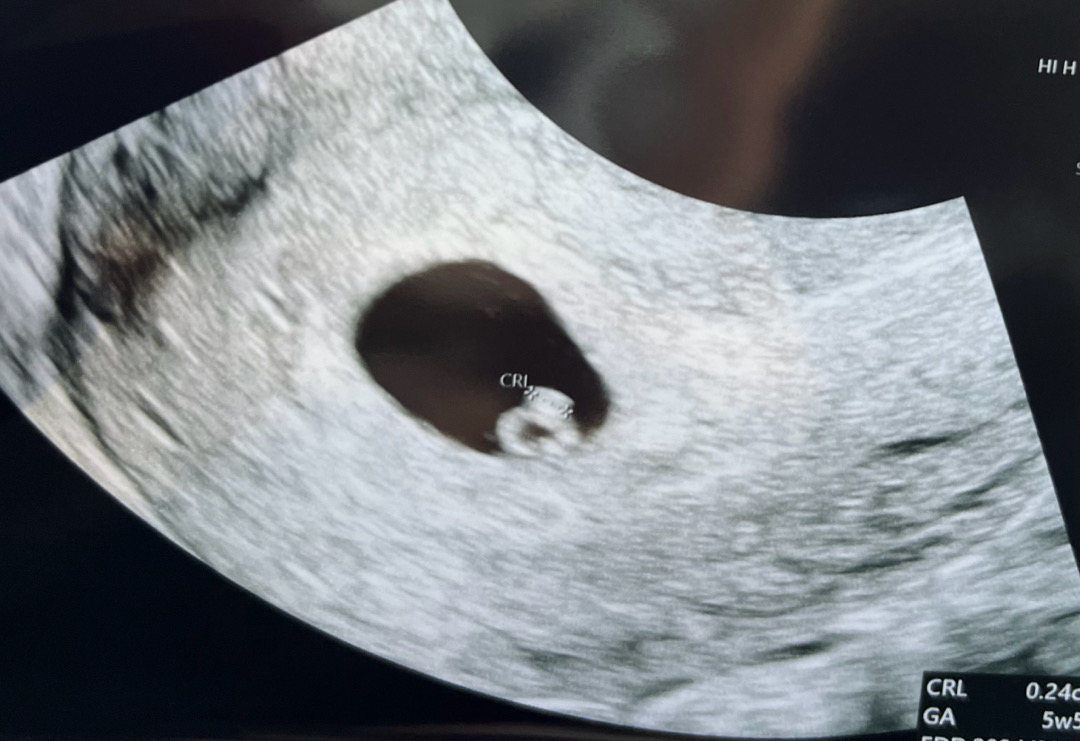

다른진료차 병원 갔다가 아기 만나고 왔어요! 지난주에는 아기집만 보였는데 오늘은 선명한 다이아반지가 딱!💍 이제 막 심장이 뛰기 시작했다고 해서 작은 심장소리를 들었고 다음주는 우렁차게 들릴거라고 하네요😇아빠랑 함께 듣게된다니 너무 좋아용ㅎㅎ 파워걱정러 엄마는 이런저런 걱정이 참 많지만.. 우리아기는 씩씩하고 건강하게만 커주길바라요🩵

6주2일에 갔는데 촘파는 5주5일로 측정됐어요ㅎㅎ